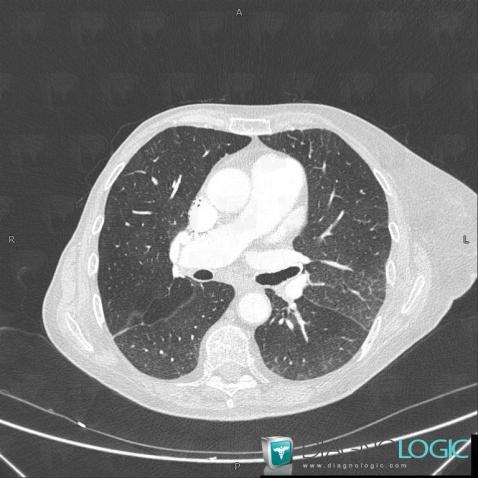

Pulmonary edema, Pulmonary parenchyma, CT

Here is the specific information in the key image above:

- Diagnosis Pulmonary edema, Location(s) Pulmonary parenchyma, with gamuts Large symetric area of ground glass opacity